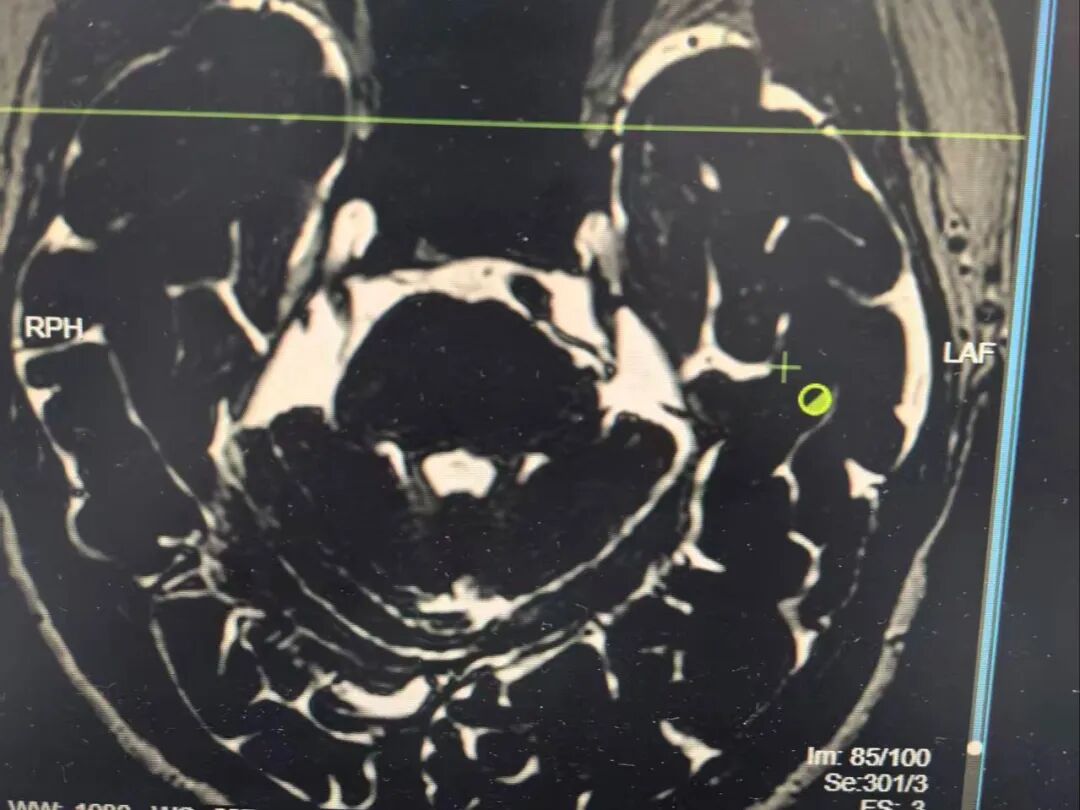

此次帮扶的核心技术提升,是刘定阳亲自现场指导并开展4台神经外科四级高难度手术,为我院功能神经外科发展提供了有力技术支撑。其中三叉神经微血管减压术作为三叉神经痛外科治疗的重要术式,在刘定阳现场带教与指导下顺利实施,为科室开展相关手术积累了关键经验。

同期,还顺利完成Chiari畸形后颅窝切开减压术、幕下深部延髓旁占位性病变切除术、左侧顶叶脑内占位病变切除术,进一步完善了我院复杂颅脑疾病手术体系,为今后我院功能神经外科的持续发展提供了有力保障。